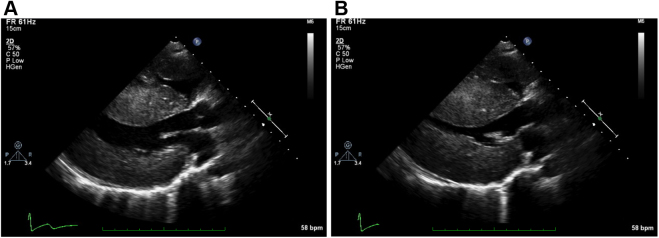

Figure 2.

Two-dimensional TTE parasternal long-axis view showing severe biventricular and septal hypertrophy during (A) diastole and (B) systole.